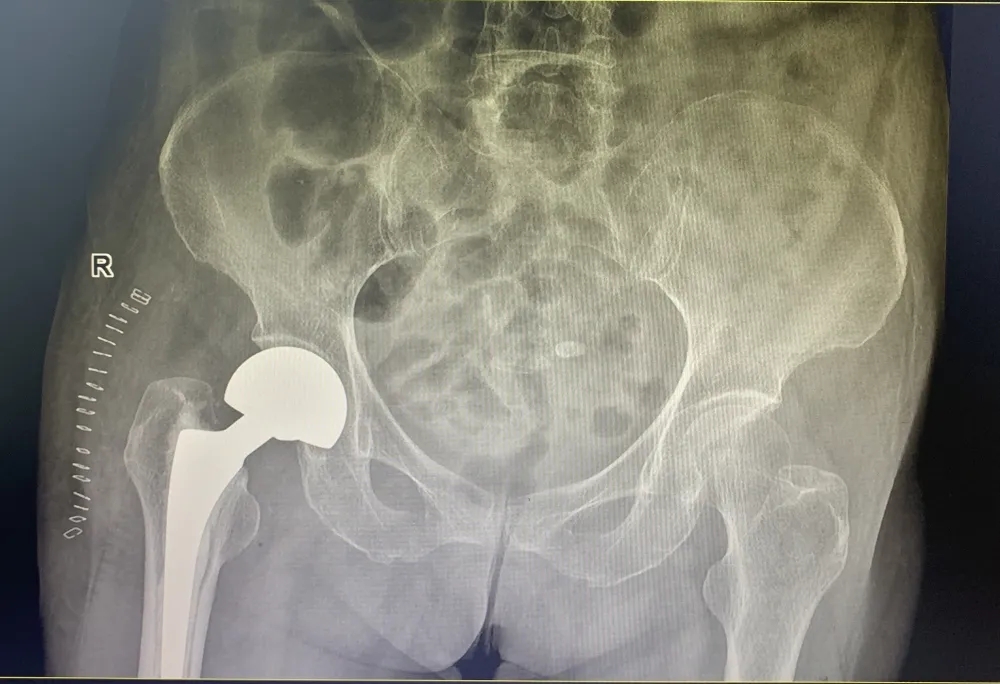

(一些术后图)

开展关节置换、关节翻修术和关节镜手术;能熟练地开展髋关节、膝关节和肩关节置换术;关节镜下的关节清理、半月板切除、半月板成形、半月板缝合、髁间窝成形、前后交叉韧带重建等手术,尤其开展了各类保膝手术,如单髁置换术、截骨矫形手术。同时开展了人工智能计算机导航辅助关节置换手术。